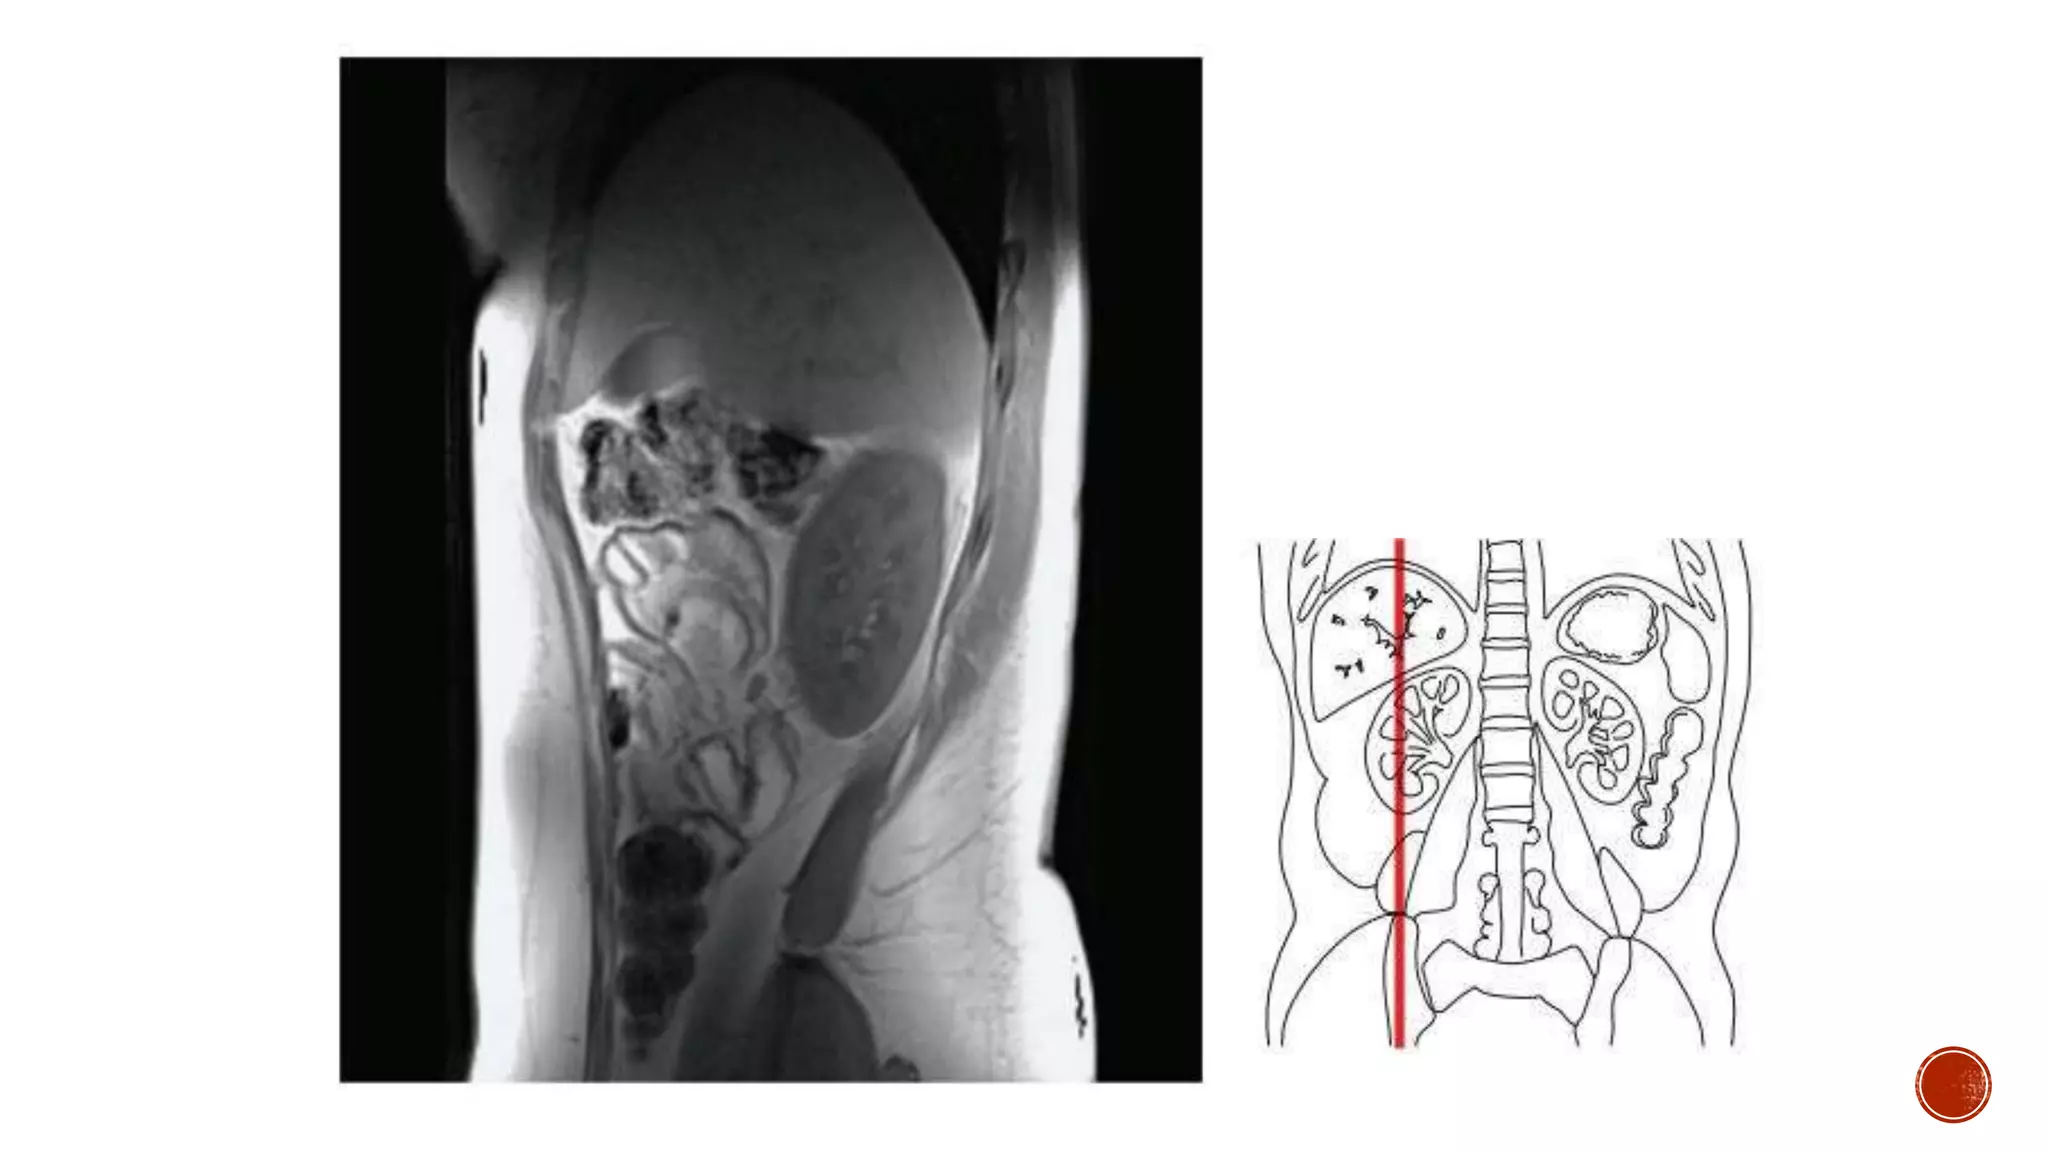

The document describes the anatomy of the abdomen and pelvis region of the human body. It lists over 40 structures and their locations, including major organs like the liver, kidneys, intestines, blood vessels and muscles of the abdominal wall and pelvis. The structures are grouped into sections focusing on different anatomical areas like the abdomen, retroperitoneum, pelvis and gluteal region.